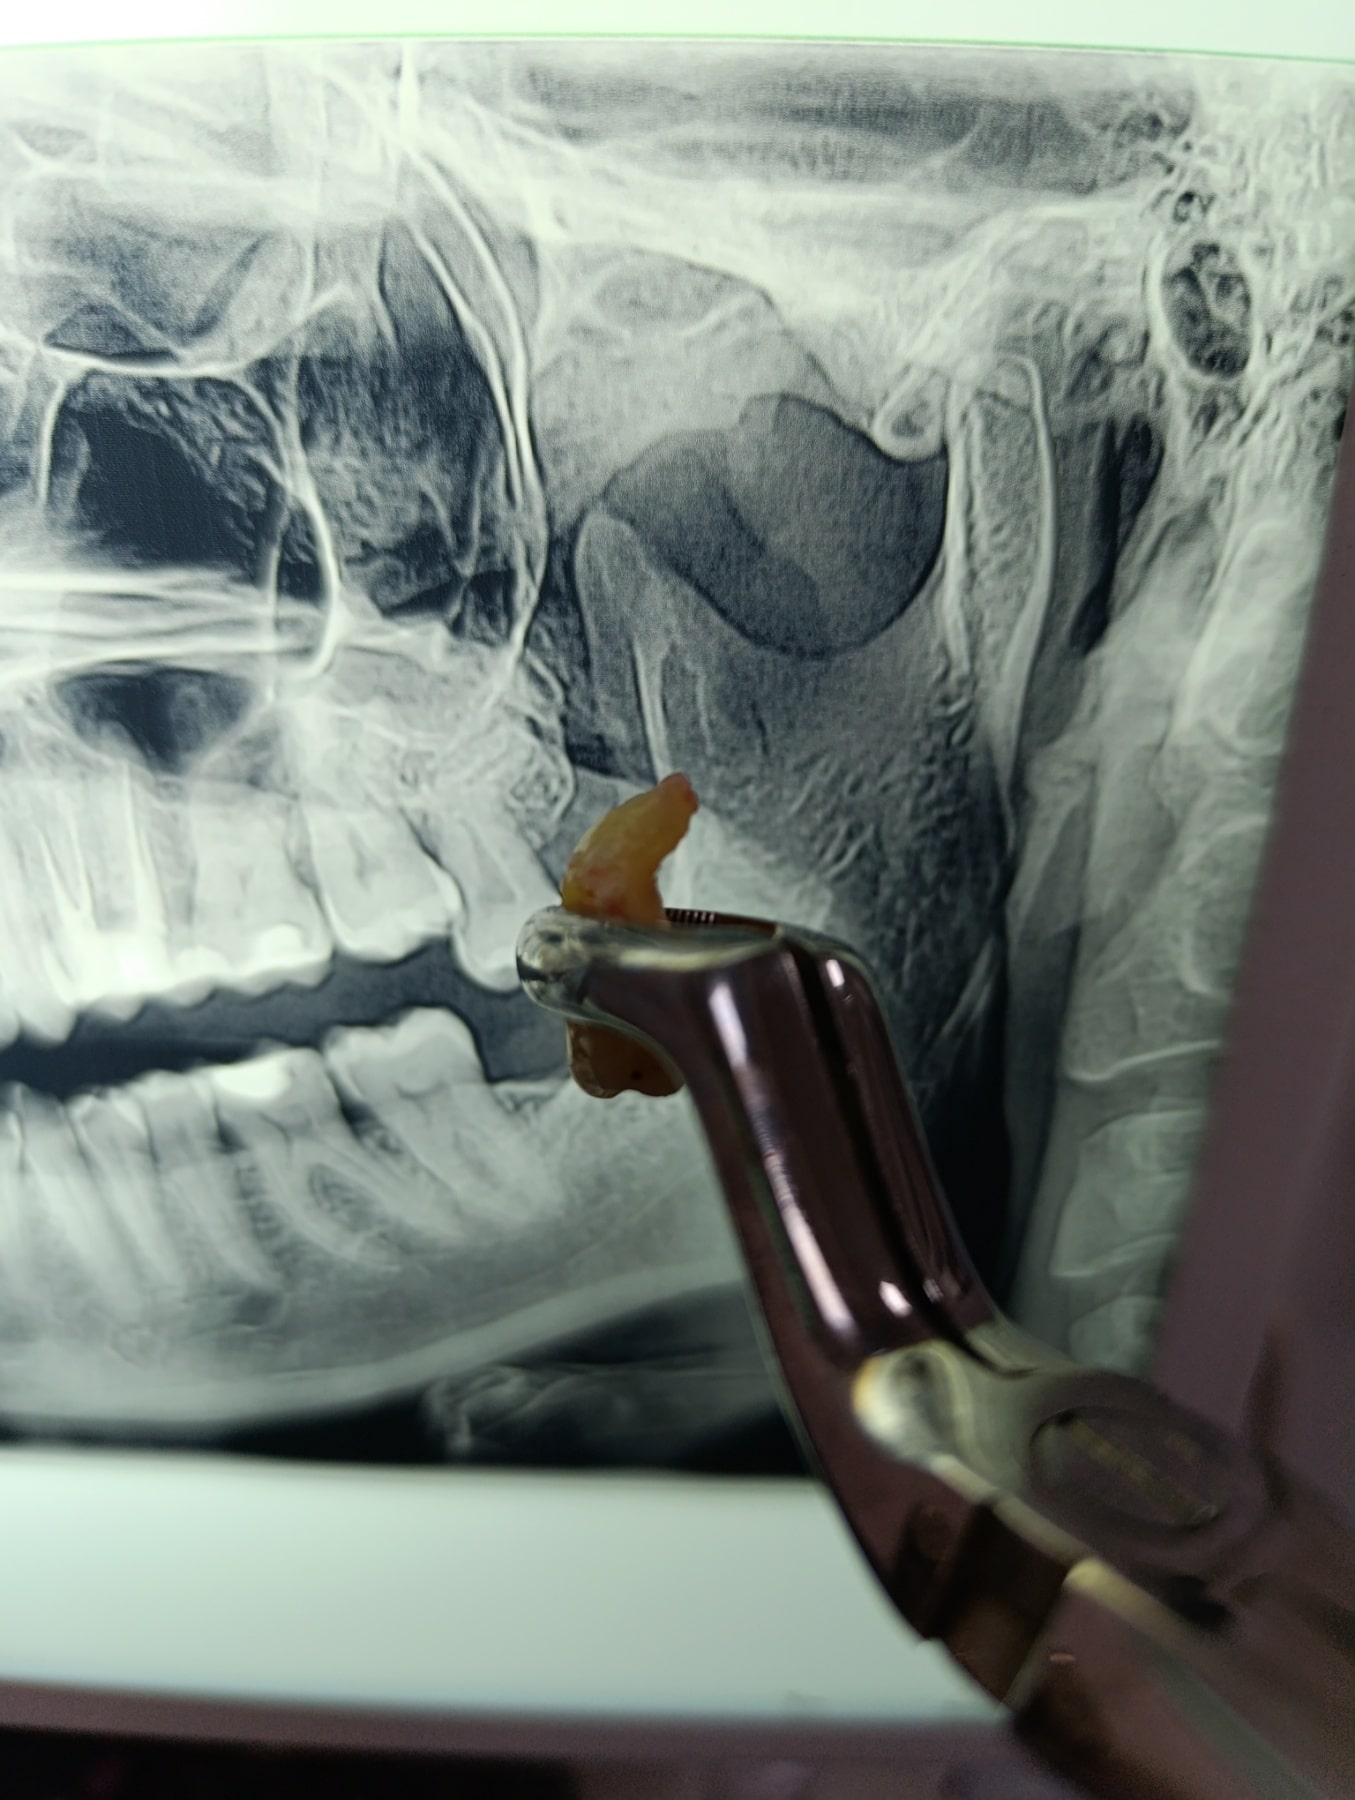

Pre zahvata, stomatolog će obaviti detaljan pregled i napraviti rendgenski snimak umnjaka kako bi video njegov tačan položaj i procenio eventualne rizike. Snimak pomaže stomatologu da planira postupak i predvidi moguće komplikacije. Osim toga, pacijent dobija uputstva o pripremi za zahvat, uključujući smernice o ishrani, lekovima i ponašanju pre samog zahvata.

Procedura počinje primenom lokalne anestezije kako bi se područje oko umnjaka potpuno umrtvilo. Stomatolog zatim pristupa umnjaku rezanjem tkiva desni i, ako je potrebno, deljenjem zuba na manje delove radi lakšeg vađenja. Nakon uklanjanja zuba, rana se šije kako bi se ubrzao proces zarastanja. Tokom cele procedure, stomatolog prati udobnost pacijenta i prilagođava postupak ako je potrebno.